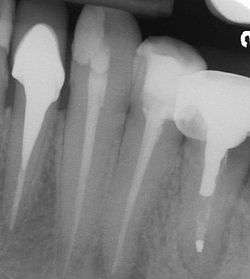

A post and core (colloquially known as a "post" or "dental post") is a type of dental restoration used either to stabilize a weakened tooth or provide an anchor for a crown. Utilized when inadequate tooth structure remains to support a traditional restoration, it consists of the insertion of a small rod (known as a "post") into the root space of an affected tooth, leaving several millimeters protruding. The protrusion is then used to support a large filling, or anchor a crown.

Post and cores divide into two main groups: prefabricated and cast. Both of these systems employ a post that is placed within the root canal of the tooth being restored. Thus the tooth must first be endodontically treated. After the endodontic procedure has been completed, and the root canal(s) is/are filled with the inert gutta percha root canal filling material, some gutta percha is removed from the canal space, usually by a series of endodontic files that prepares and shapes the root canal. The space that exists coronal to the remaining gutta percha, called the post space, is now available within which to place a post. It is desirable to leave sufficient root filling material in the apical area to maintain an apical seal. This procedure does not even require local anesthesia as the tooth has long been dead after the root canal treatment and no pain is felt.

In the picture at right, the two teeth on the extreme left and right are the ones under discussion. The two teeth in the middle have been endodontically treated, but do not have post and cores.